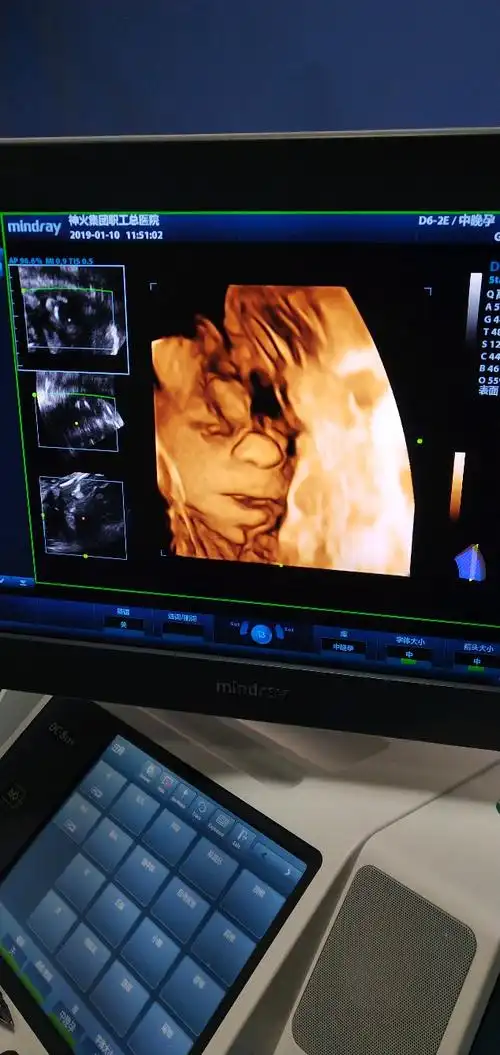

四维彩超鼻子大,四维彩超长相很丑,这些事都不需要纠结,因为四维彩超

"看到娃四维照,我以为怀了外星人",孕期四维彩超为何丑出天际

四维彩超和宝宝的长相差别大吗?这些特征存在误差,丑俊难辨

怀七个月做的四维,哈哈,宝妈们看看这是男孩女孩